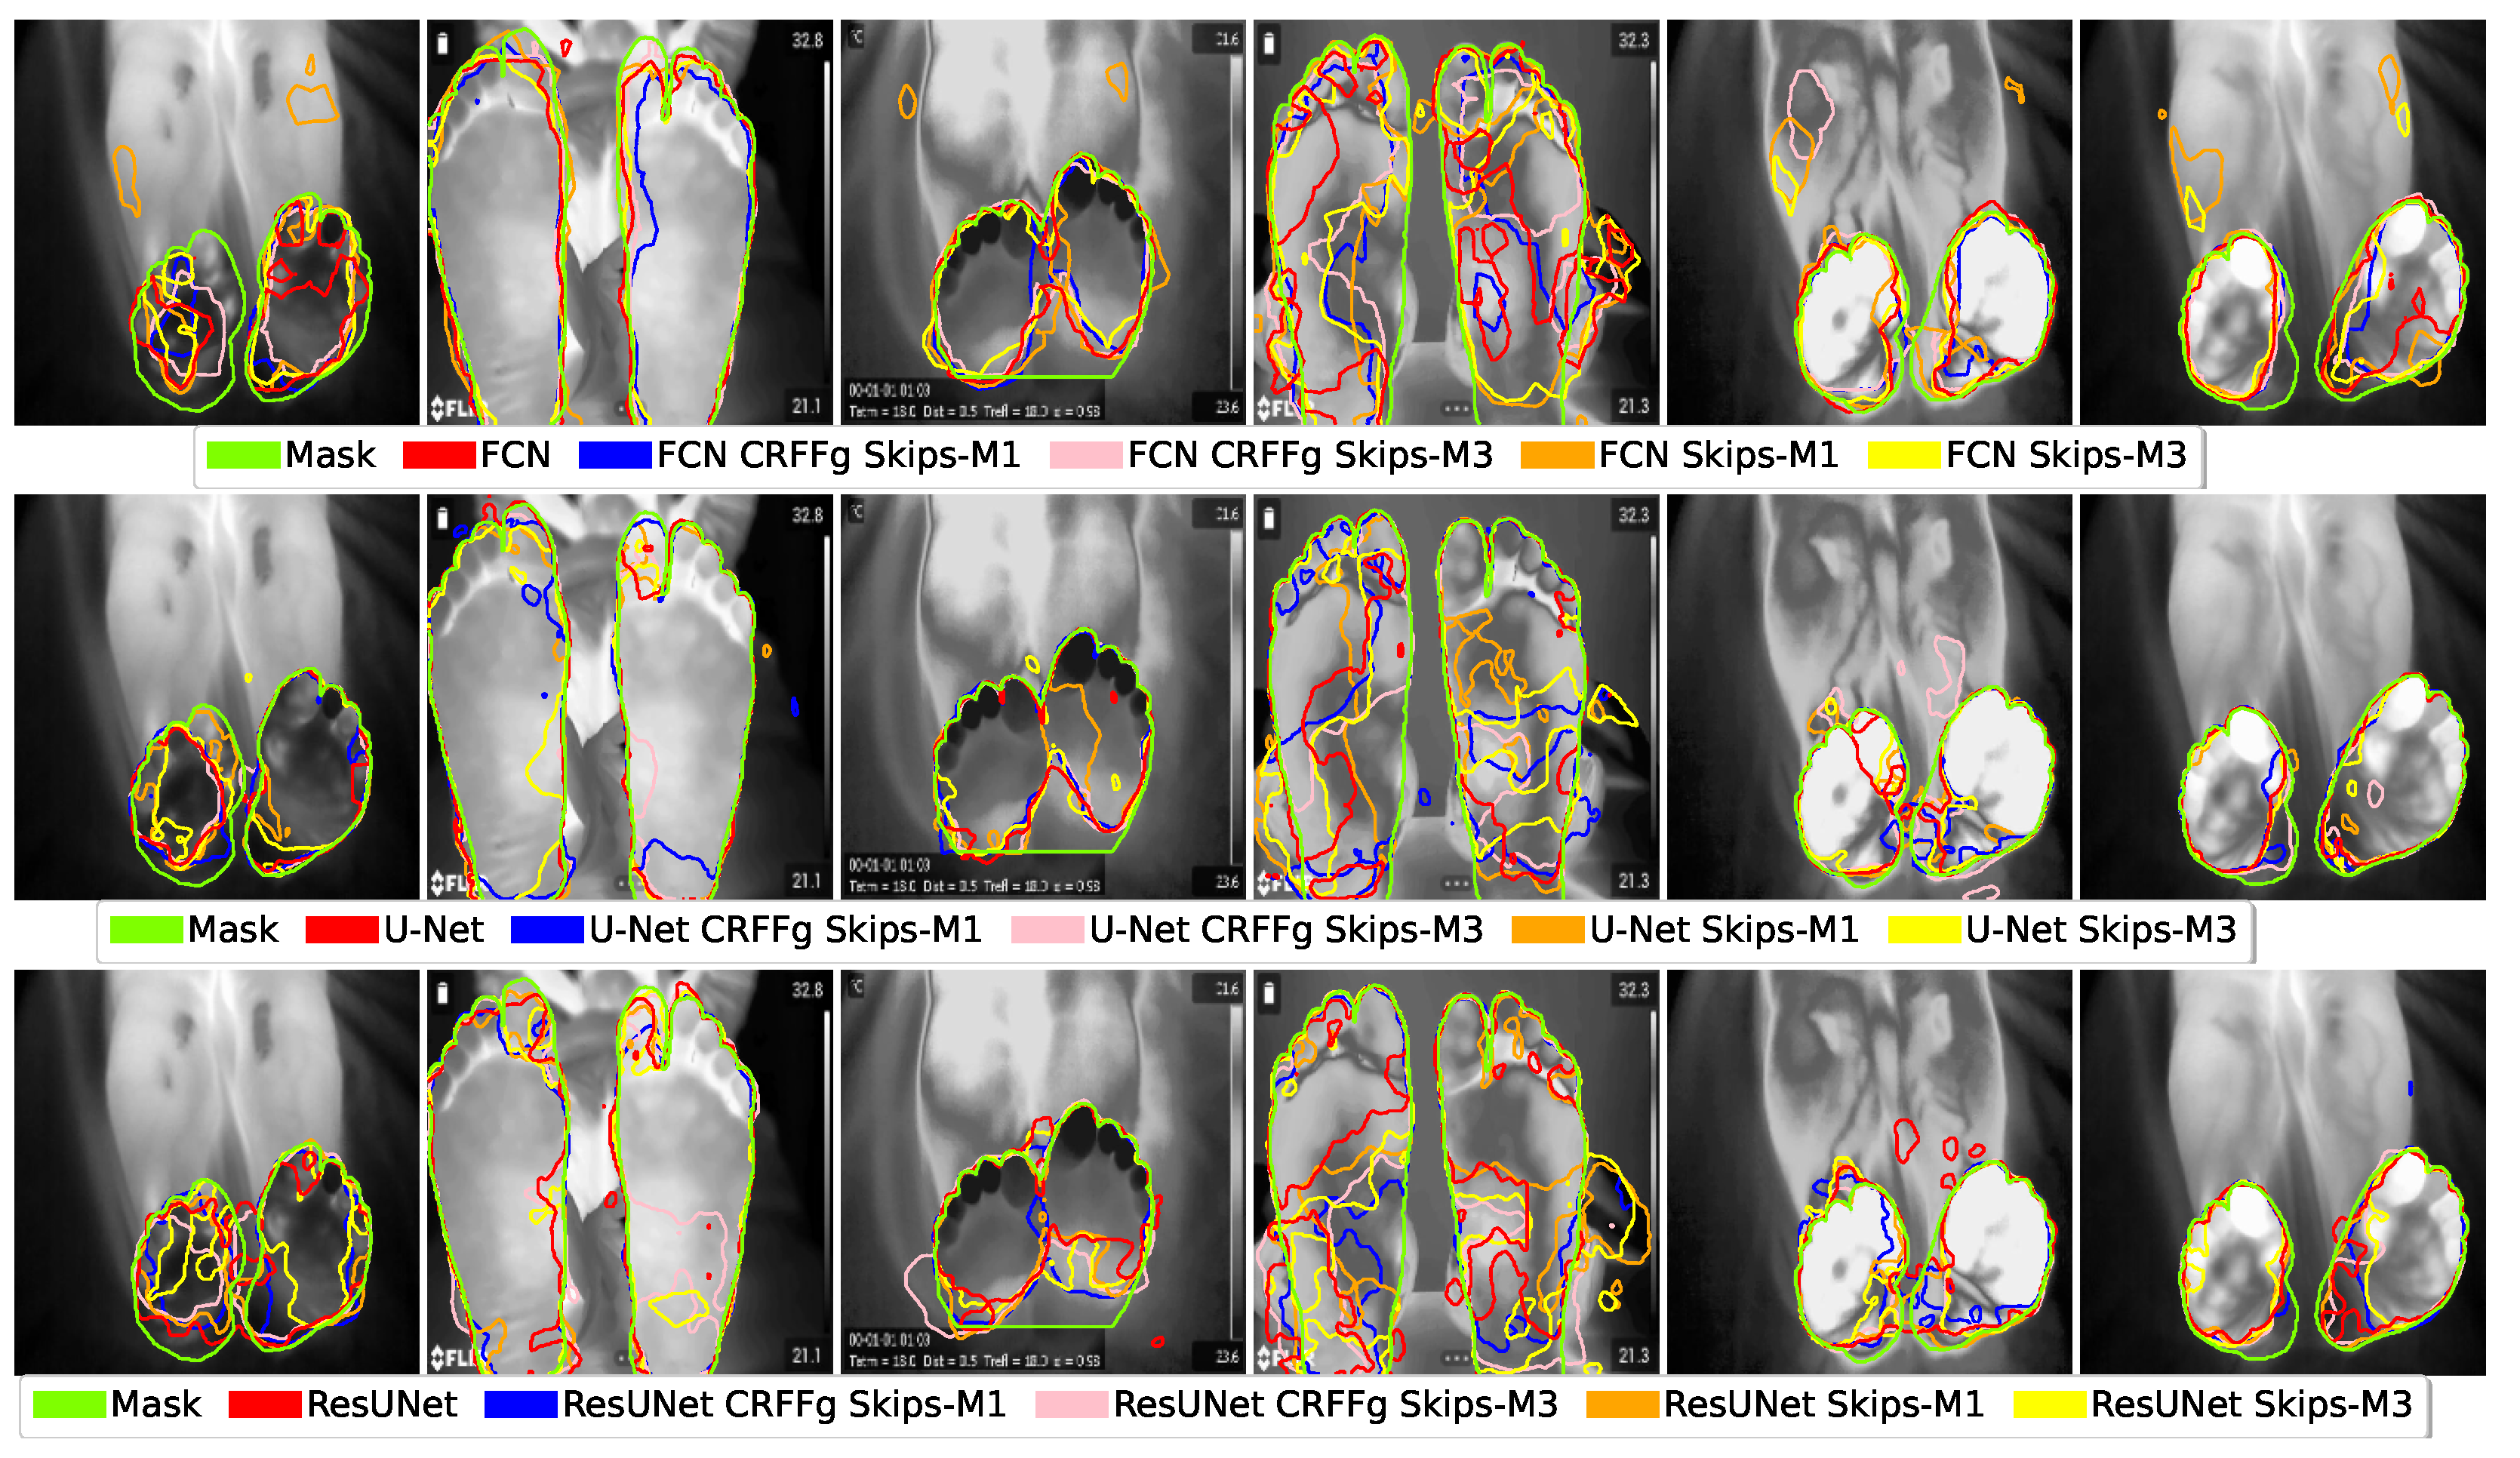

4.1. Visual Inspection Results